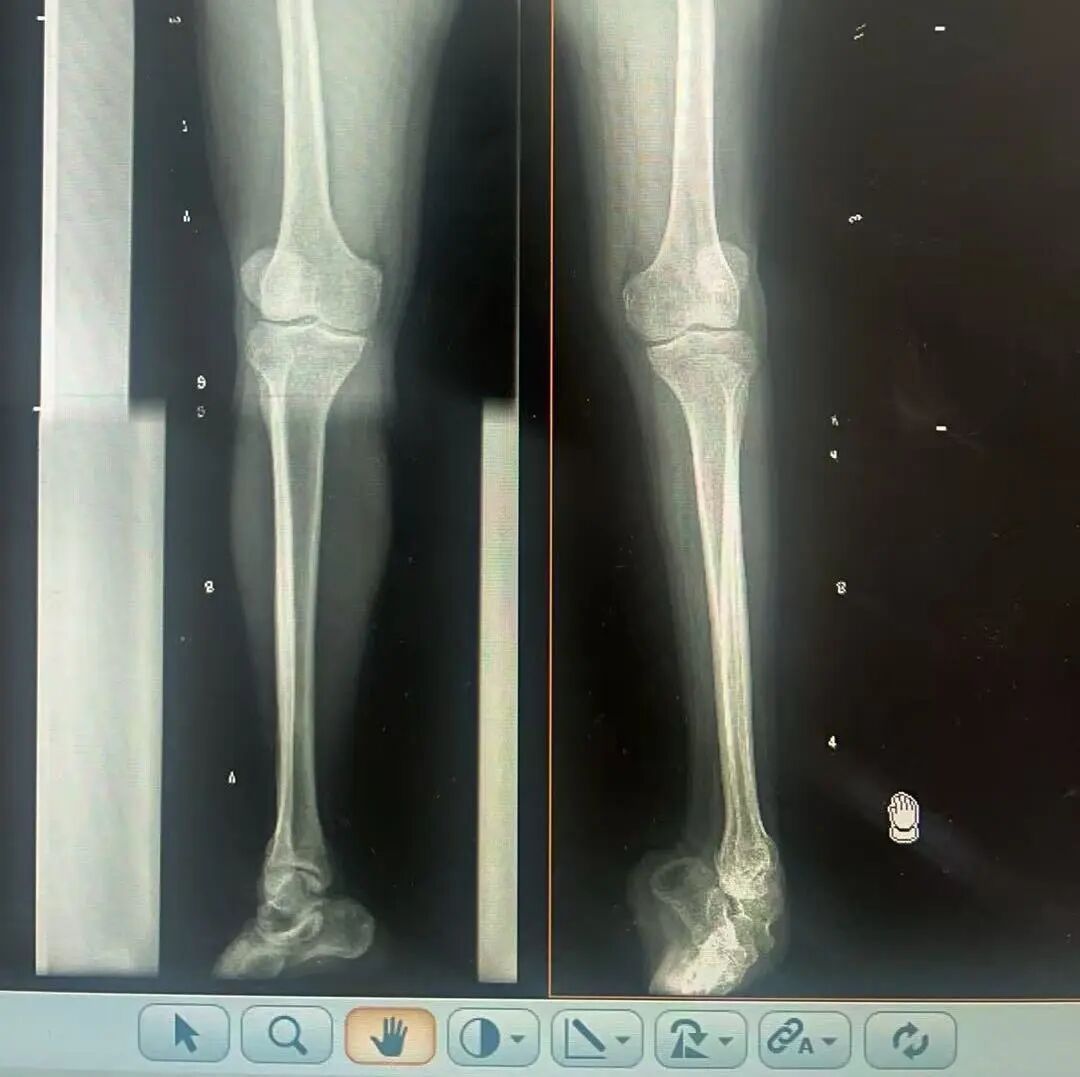

術(shù)前X光片 VS 術(shù)后治療效果

三十八年前,一紙“脊髓灰質(zhì)炎”的診斷,讓陽先生的人生染上了陰霾。闖過了急性期的鬼門關(guān),但后遺癥——嚴重的左踝馬蹄內(nèi)翻足畸形,是一道無形的枷鎖,禁錮著他的成長與自由。骨盆傾斜、雙腿不等長、左腳嚴重內(nèi)翻,他成長成人中行走的每一步,都伴隨著難以言說的艱辛。

骨科隨即為陽先生進行了全面的檢查。診斷明確而復(fù)雜:陽先生患有脊髓灰質(zhì)炎后遺癥、左踝馬蹄內(nèi)翻足、骨盆傾斜……面對這張沉甸甸的診斷書,由肢體功能重建顯微修復(fù)學(xué)科組長鄭群龍所帶領(lǐng)的醫(yī)療團隊沒有畏懼,“這是一個家庭38年的堅守與期盼,我們必須全力以赴”

針對陽先生的復(fù)雜情況,鄭群龍醫(yī)師團隊制定了詳盡的手術(shù)方案:左踝關(guān)節(jié)融合+馬蹄足畸形矯正+跟腱延長+外固定架固定術(shù)。手術(shù)的核心,正是伊里扎洛夫技術(shù)。這項技術(shù)如同精密的“時空建筑學(xué)”,通過微創(chuàng)安裝環(huán)形外固定架,前足-后足安裝鋼環(huán),再將足的鋼環(huán)與脛骨的固定鋼環(huán)在踝關(guān)節(jié)前、后、左、右用帶關(guān)節(jié)的螺紋桿連接,由此構(gòu)建成一個能體外牽拉調(diào)控的三維立體構(gòu)型,在術(shù)后進行精準、緩慢的調(diào)整,一寸一寸逐步將畸形的骨骼、軟組織恢復(fù)到正常位置。